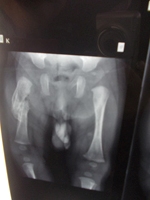

Severe trauma is usually required to injure the lower limb in children. Usual site of fracture is through the diaphysis or metaphysis of bone. Foot injuries are also common in children. These fractures have good remodelling potential hence they can be treated with simple plasters. However femur fractures in older children will usually require nailing or plating. Though the fractures heal quickly, the children sometimes need a longer time to recover and hence will continue to limp even after plaster removal. The children start walking once their pain decreases.